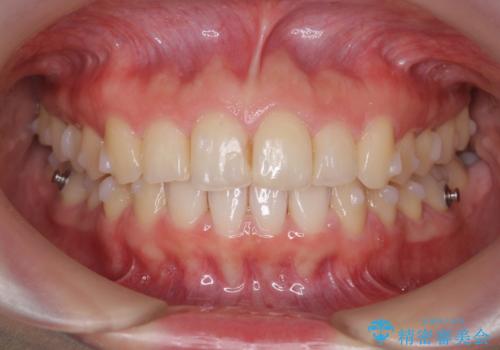

出っ歯に見える前歯の改善 部分ワイヤーとマウスピース矯正

最終的な前歯の並びに大変満足いただくことができました。